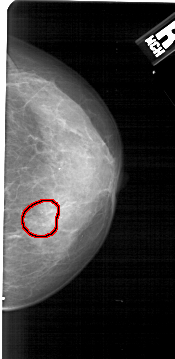

A_1431_1.RIGHT_CC

RIGHT_CC LINES 5026 PIXELS_PER_LINE 2446 BITS_PER_PIXEL 12 RESOLUTION 43.5 OVERLAY

FILE: A_1431_1.RIGHT_CC.OVERLAY

TOTAL_ABNORMALITIES 1

ABNORMALITY 1

LESION_TYPE CALCIFICATION TYPE AMORPHOUS DISTRIBUTION CLUSTERED

ASSESSMENT 4

SUBTLETY 3

PATHOLOGY BENIGN

TOTAL_OUTLINES 1

BOUNDARY